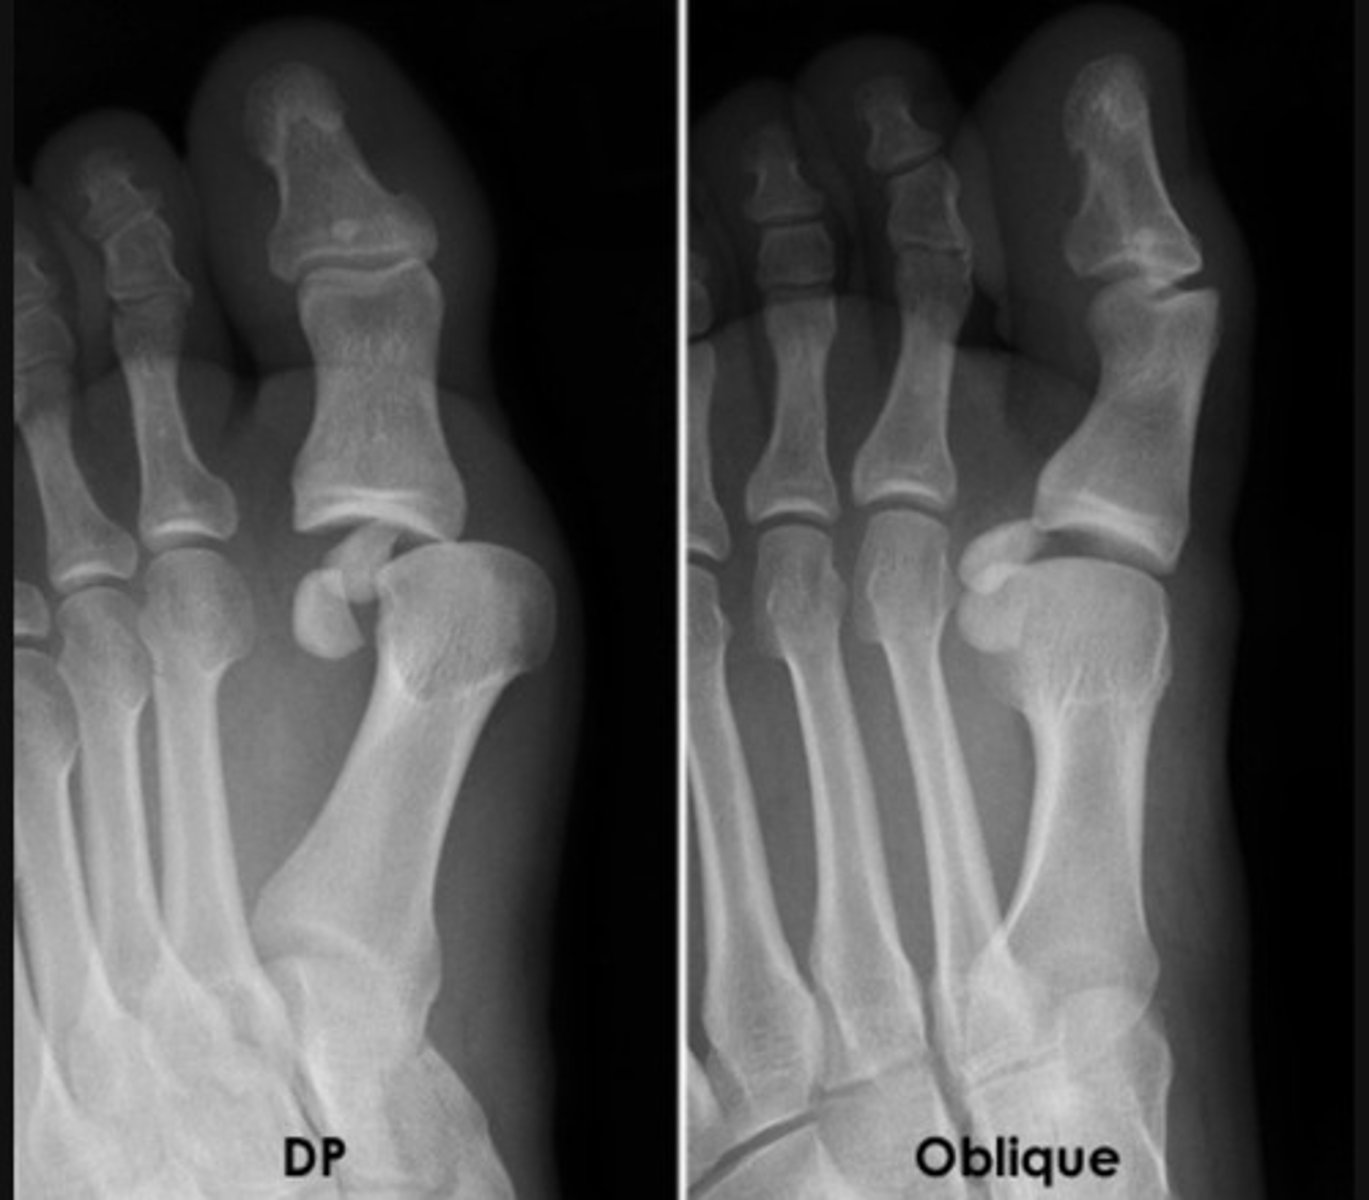

Lisfranc injury

base of 5th metatarsal fracture

dislocation of the proximal phalanx of the big toe at the MTPJ (metatarsophalangeal joint)